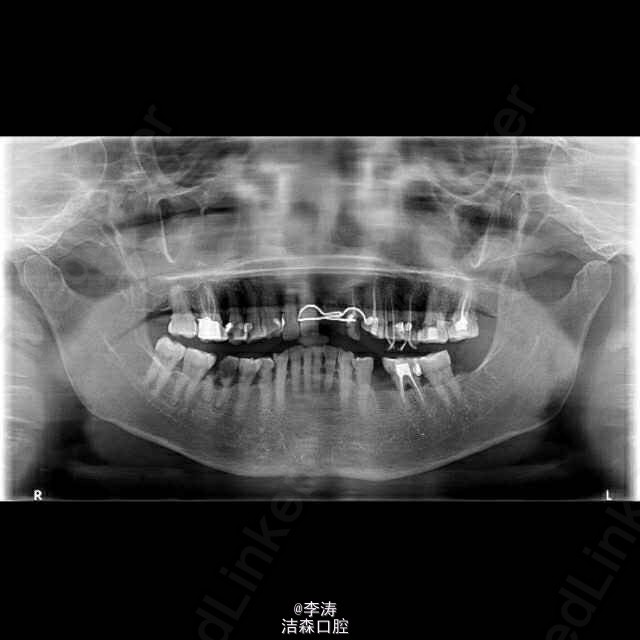

多颗牙牙痛根管治疗1例

这是接诊的最难的一例病例,患者65岁女性,主诉牙齿疼痛,检查基本上全口邻面深龋,治疗完左边,右边又痛,结果是全口多数牙都被根管治疗,治疗完准备不做冠,又被咬崩,结果又不得不将根管治疗的牙全做冠。